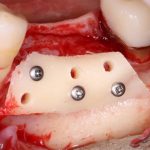

Я зафиксировал костный блок практически без адаптации на несколько винтов. Обрати внимание, что винты находятся в зоне, где не планируется установка имплантатов. Фиксация должна быть надежной, поскольку мне еще предстояла подготовка лунок для имплантатов. Трех винтов для этого вполне достаточно.

Изоляция области аутографта и имплантатов барьерной мембраной.

Конкретно в этом клиническом случае между костным аутотрансплантатом, ложем и имплантатами есть пустое пространство. Если его не изолировать от мягких тканей, они прорастут и осложнят интеграцию аутографта. Поэтому я решил перекрыть костный блок барьерной мембраной, пусть это делает хирургическую операцию немного дороже.

— я использовал барьерную мембрану Geistlich Bio-Gide, которая имеет две разные поверхности: с одной стороны она рыхлая «адгезивная», с другой — гладкая и прочная. Как укладывать — на результат не влияет, но в плане удобства рыхлую поверхность мы «приклеиваем» к тому, на чем требуется барьерную мембрану удержать. В данном случае хотелось бы удержать её на костной поверхности — следовательно, мы укладываем её рыхлой поверхностью к кости.

— ты знаешь, что барьерная мембрана может выполнять две функции, каркасную и изолирующую. Первая функция требует обязательной фиксации и натяжения, вторая — нет. В нашем случае «каркасом» регенерата является костный блок, а барьерная мембрана нужна только для изоляции. Поэтому она не требует натяжения и фиксации пинами.

После я внимательно проверил, что костный блок и имплантаты полностью перекрыты. Теперь рану можно ушивать.